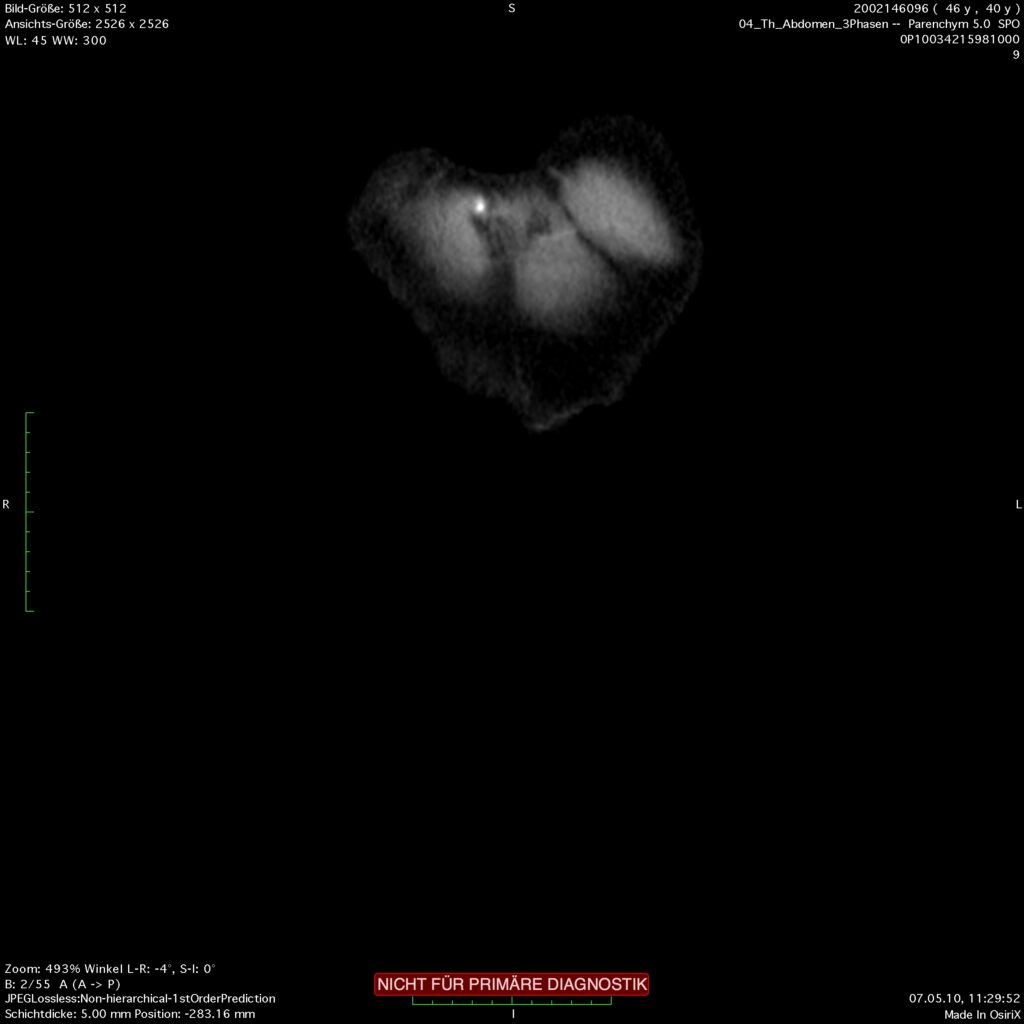

Das klinische Erscheinungsbild ist geprägt von einem dumpfen Oberbauchschmerz, der typischerweise in den Rücken ausstrahlt. An den Flanken und periumbilical können sich Einblutungen bilden. Dieses sog. Grey-Turner bzw. Cullen-Zeichen spricht für eine schwer fortgeschrittene Pankreatitis und ist prognostisch ungünstig. In der Labordiagnostik sind die Pankreasenzyme erhöht, spezielles Augenmerk sollte auch auf die Cholestasewerte gerichtet werden, um eine mögliche biliäre Ursache erkennen zu können. Im Verlauf der Erkrankung kann eine Computertomografie des Abdomens das Ausmaß der Nekrosen sichtbar machen, zu Begninn hat diese Art der Diagnostik jedoch eine geringe Aussagekraft.